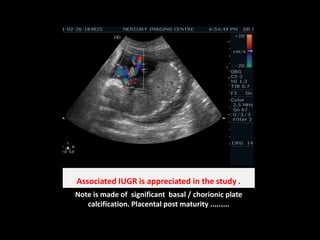

Associated IUGR is appreciated in the study .Note is made of  significant  basal / chorionic plate calcification. Placental post maturity .........

Associated IUGR isappreciated in the study .Note is made of significant basal / chorionic plate calcification. Placental post maturity .........